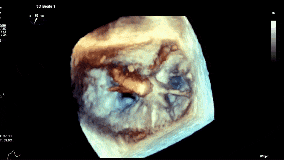

术前超声影像

3D

3D彩

术前超声